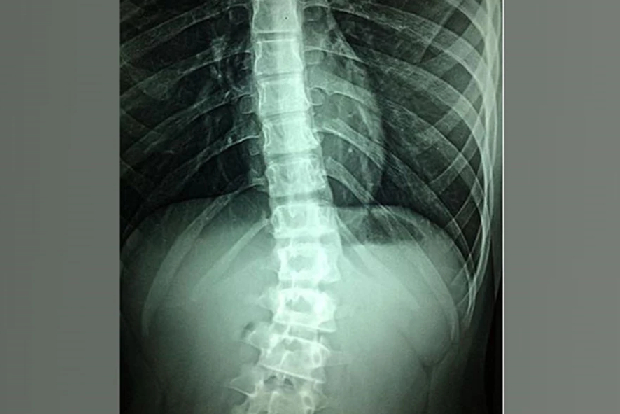

Scientists reported high-frequency SCS proved more effective at improving perceived pain reduction (PPR) than low-frequency SCS in patients studied,...